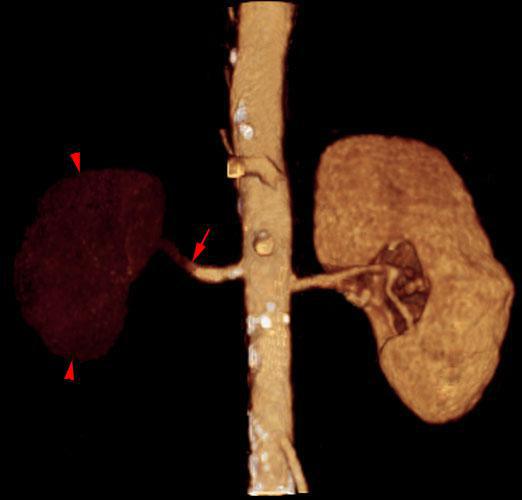

Infartos renales múltiples